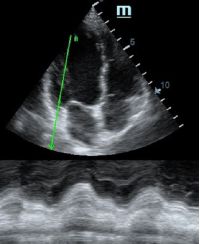

Но как же провести стандартные измерения в М-режиме, если мы его не использовали? На помощь приходит функция Free Xros M – анатомический М-режим. Имея записанную в память прибора видео петлю, мы можем провести линию М-режима в любом месте, при этом корректируя изначально не оптимальный угол.

MAPSE - амплитуда движения латерального кольца митрального клапана, позволяет рассчитать фракцию выброса по формуле EF = 4.8 × MAPSE (mm) + 5.8, очень быстрый и гораздо более точный («прародитель Strain») метод чем широко распространенный метод Teicholtz. В современных приборах можно легко добавить свою формулу при отсутствии ее в стандартном калькуляторе. Главным условием является проведение линии М-режима параллельно стенке левого желудочка в апикальном четырехкамерном сечении, что легко достигается при использовании функции Free Xros.